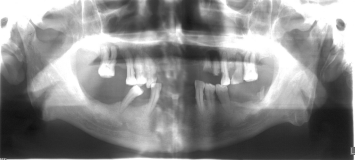

2017年2月28日曲面断层示:口腔内多颗牙齿缺失,分别为右上126、左上12、右下1247、左下1267,其中双侧上下切牙牙槽骨隐见牙槽窝,较前片稍变浅,片中所示牙槽骨吸收明显,遗留牙齿的牙槽骨吸收均达根长的1/2以上。

2017年2月28日曲面断层(胶片)